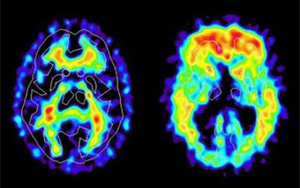

新冠帶來新的“醫(yī)療壓力”:阿爾茨海默病的風(fēng)險飆升50%-80%

研究發(fā)現(xiàn)感染新冠病毒的老年人患阿爾茨海默病的風(fēng)險因素增加了50%-80%。